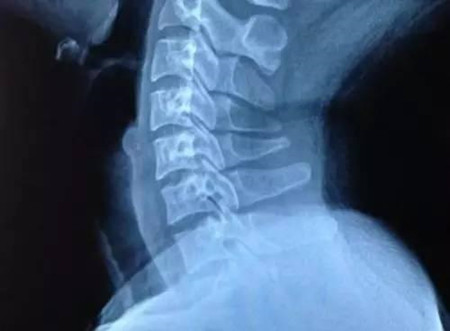

隨著現(xiàn)在人們生活節(jié)奏的不斷加快,人們所面對的生活壓力也變得越來越大,生活中各方面的壓力也給現(xiàn)代人們的身體健康帶來了一定的影響,尤其是現(xiàn)在很多上班族容易患有頸椎病,導致頸椎病發(fā)生的原因有很多種,對于頸椎病的患者應該要引起重視,還要避免過度勞累,可以適當?shù)倪M行一些活動,下面小編和大家一起來了解一下,頸椎病睡覺的時候該睡高枕頭好還是矮枕頭好。

首先,我們大家一起來了解一下,頸椎病睡覺的時候該睡高枕頭好還是矮枕頭好,對于頸椎病的患者,最好可以選擇適合自己的枕頭,比拳套高一點的高度是最佳的高度是比較適合頸椎病患者的。

其次,在我們的日常生活中,不少人患有頸椎病,導致頸椎病發(fā)生的原因有很多種,尤其是現(xiàn)在很多上班族容易患有頸椎病,頸椎病所帶來的危害也是比較嚴重的,對于頸椎病的患者要盡早的接受改善。

現(xiàn)在患有頸椎病的患者比較多,導致頸椎病發(fā)生的原因也是比較多的,對于頸椎病的患者應該要引起重視,應該避免過度勞累,適當?shù)倪M行體育鍛煉,對于身體是比較好的。